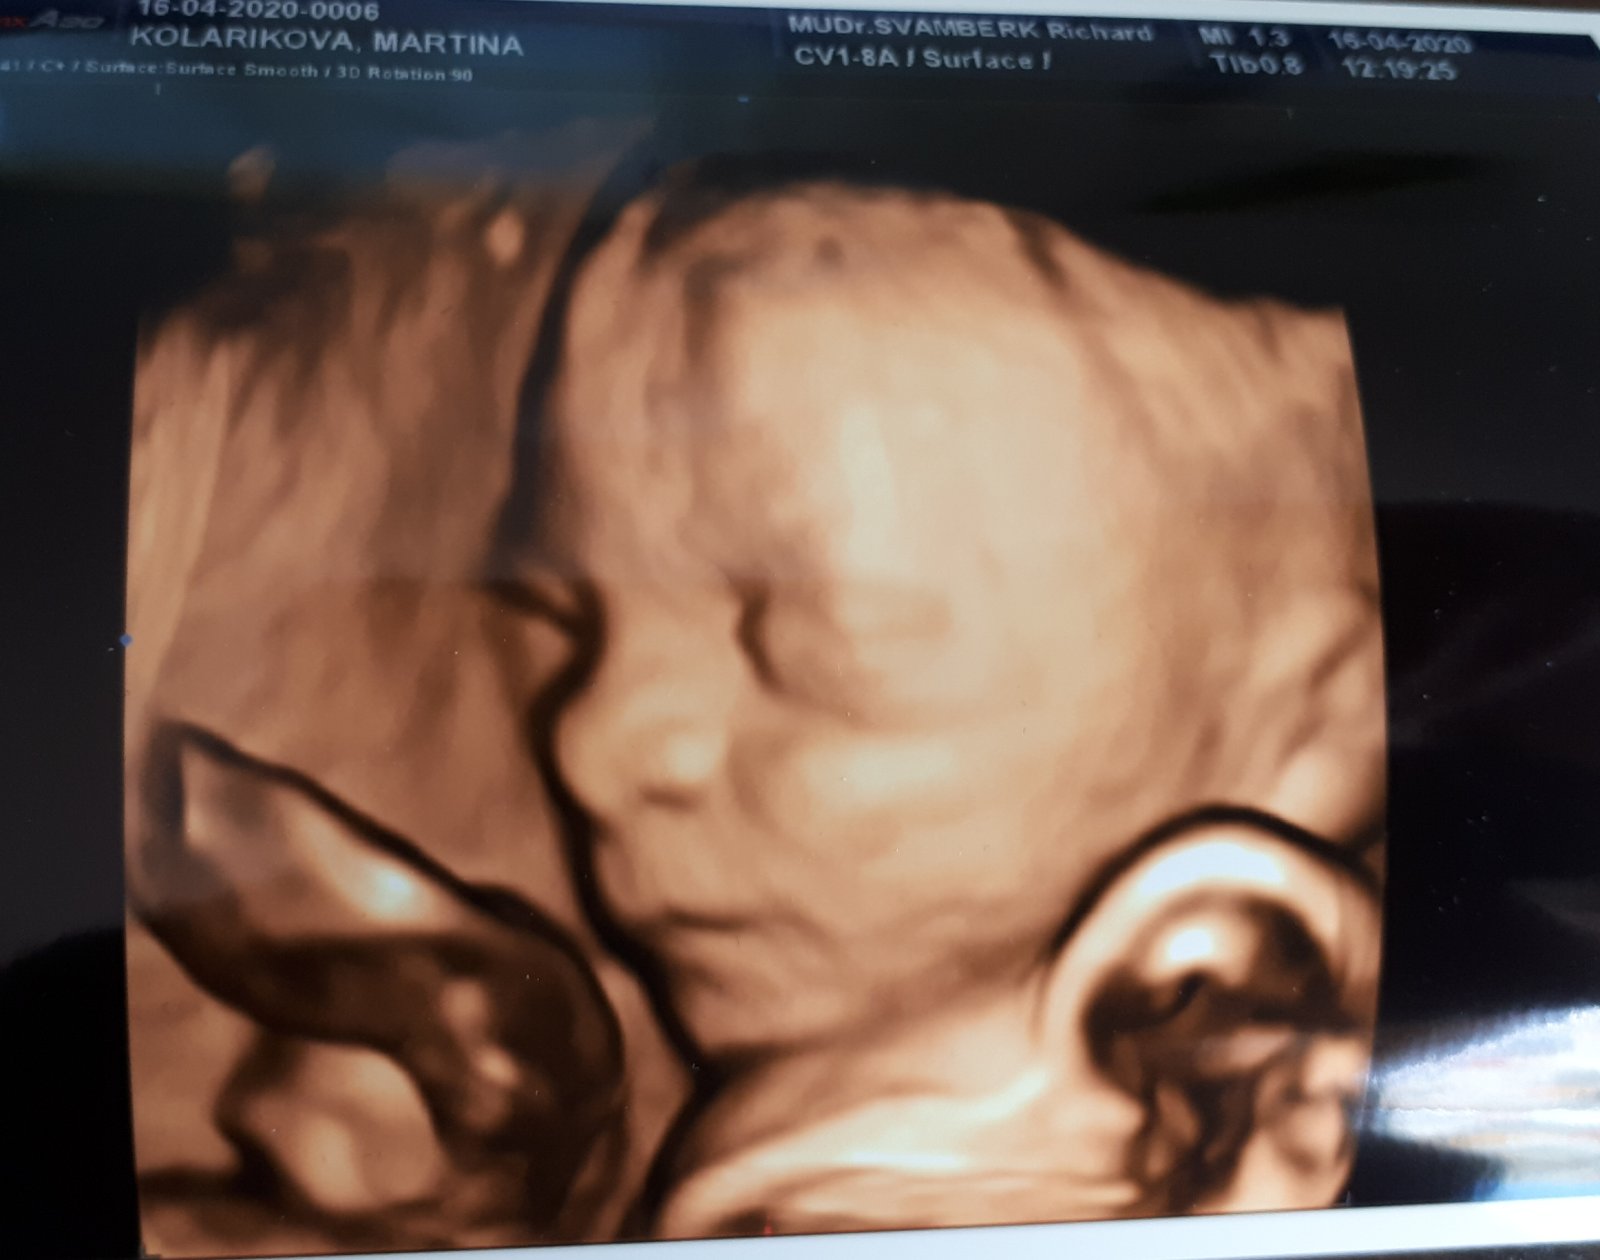

16. 4. 2020

- 24+3 tt - dnes kontrola a vše v pořádku, moje váha 75 kg

- pohyby cítím pořád, mimčo je živé hlavně večer 😜 jinak občas zácpa a křeče v nohách, únava, ale jinak se cítím fajn...

- dnes také 3D UTZ - byla to nádhera a miminko je strašně moc podobné mladšímu synovi Jáchymkovi. Mimi je živé, pořád se mrskalo, otevíralo pusinku - prostě božííííí ♥